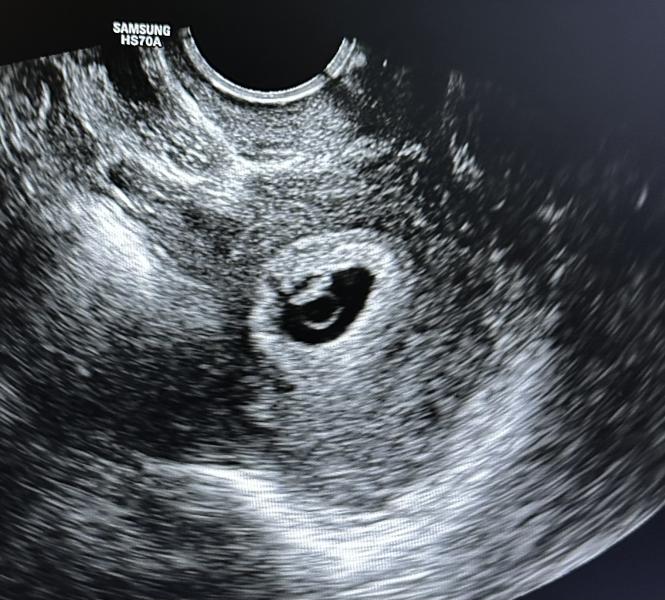

Первое УЗИ после криопереноса: что показало на сроке 6 недель и 3 дня? СБ и 29 ДПП

Наше первое узи и сб ❤️ 29 дней после криопереноса. Срок 6 недель 3 дня по месячным